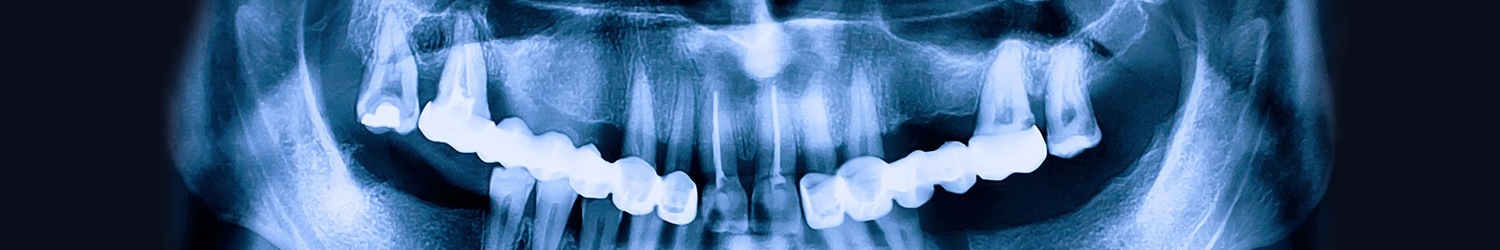

In order for dental implants to be successful, the presence of healthy and adequate bone is essential. Many causes lead to bone loss and the formation of defects that may require augmentation. Bone grafting may be used to regenerate a small or large defect.

Different types of grafts and grafting materials can be used. The traditional standard bone graft material is to use the patient’s own bone. The graft can be obtained from different areas sites such as the mandible (lower jaw), hip bone, etc. and placed in the area of the defect. This bone graft will then re-vascularize and become incorporated. Many other options are also available as well and these materials have dramatically improved in predictability over the years.

Bone regeneration and bone grafting work hand-in-hand in order to restore these defects. Bone regeneration is the ability of your body to form new bone. Many techniques and materials used today enhance the patient’s ability to form new bone. Different types of membranes and materials can be used to help isolate the bone graft and enhance the formation of new bone.